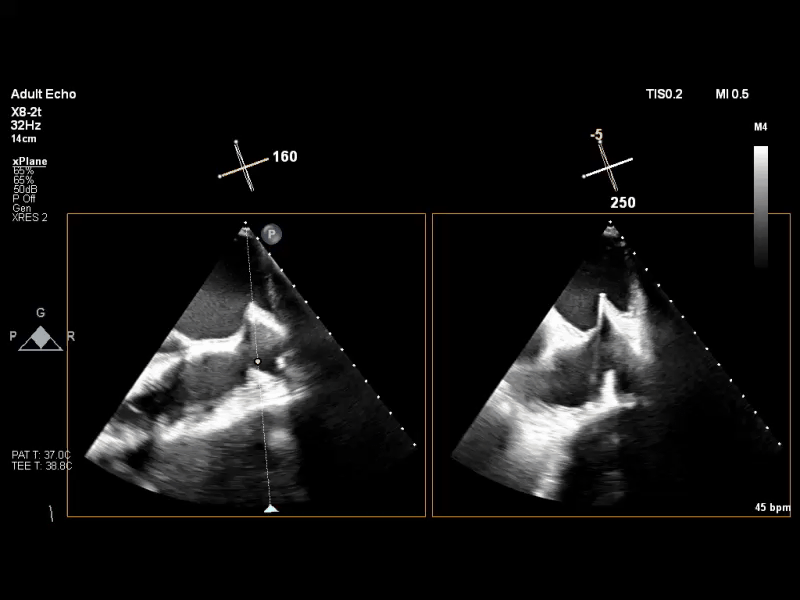

术前TEE XPLANE COLOR

经食道超声心动图(TEE)提示:二尖瓣病变Carpentier II型,DMR,二尖瓣2区反流及P2腱索断裂并瓣叶脱垂,Gap 6 mm,Width 15 mm, 瓣口面积6.7 cm²,2区前叶长20 mm,后叶长19 mm。MR4+,反流束来自于2区,偏心性反流束,指向前叶;VC 11 mm。房间隔穿刺空间约4.5 cm。